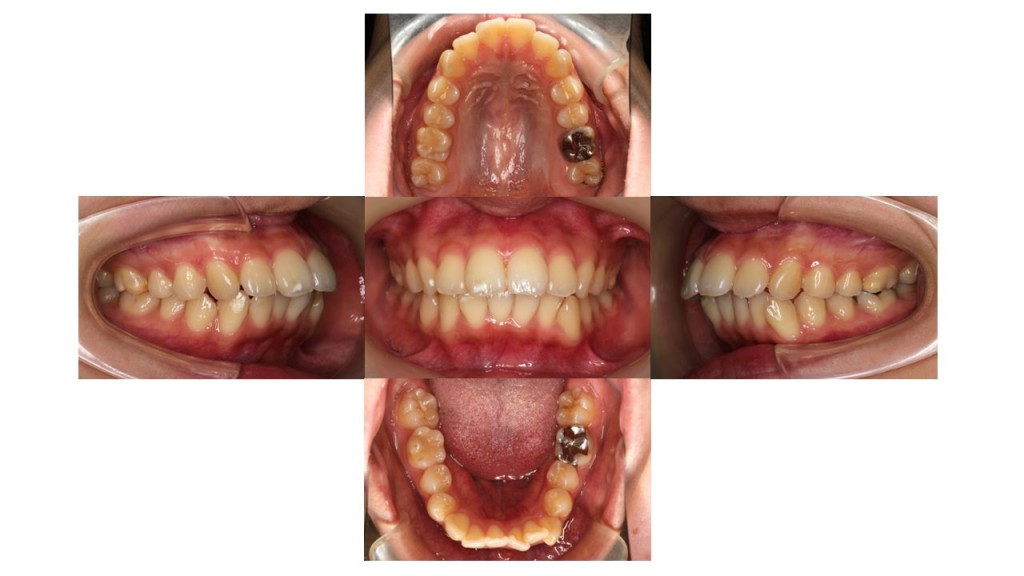

初診時の口腔内の状態です。

上の歯が出ていて、前歯がかみ合っていないことにお悩みでご来院されました。